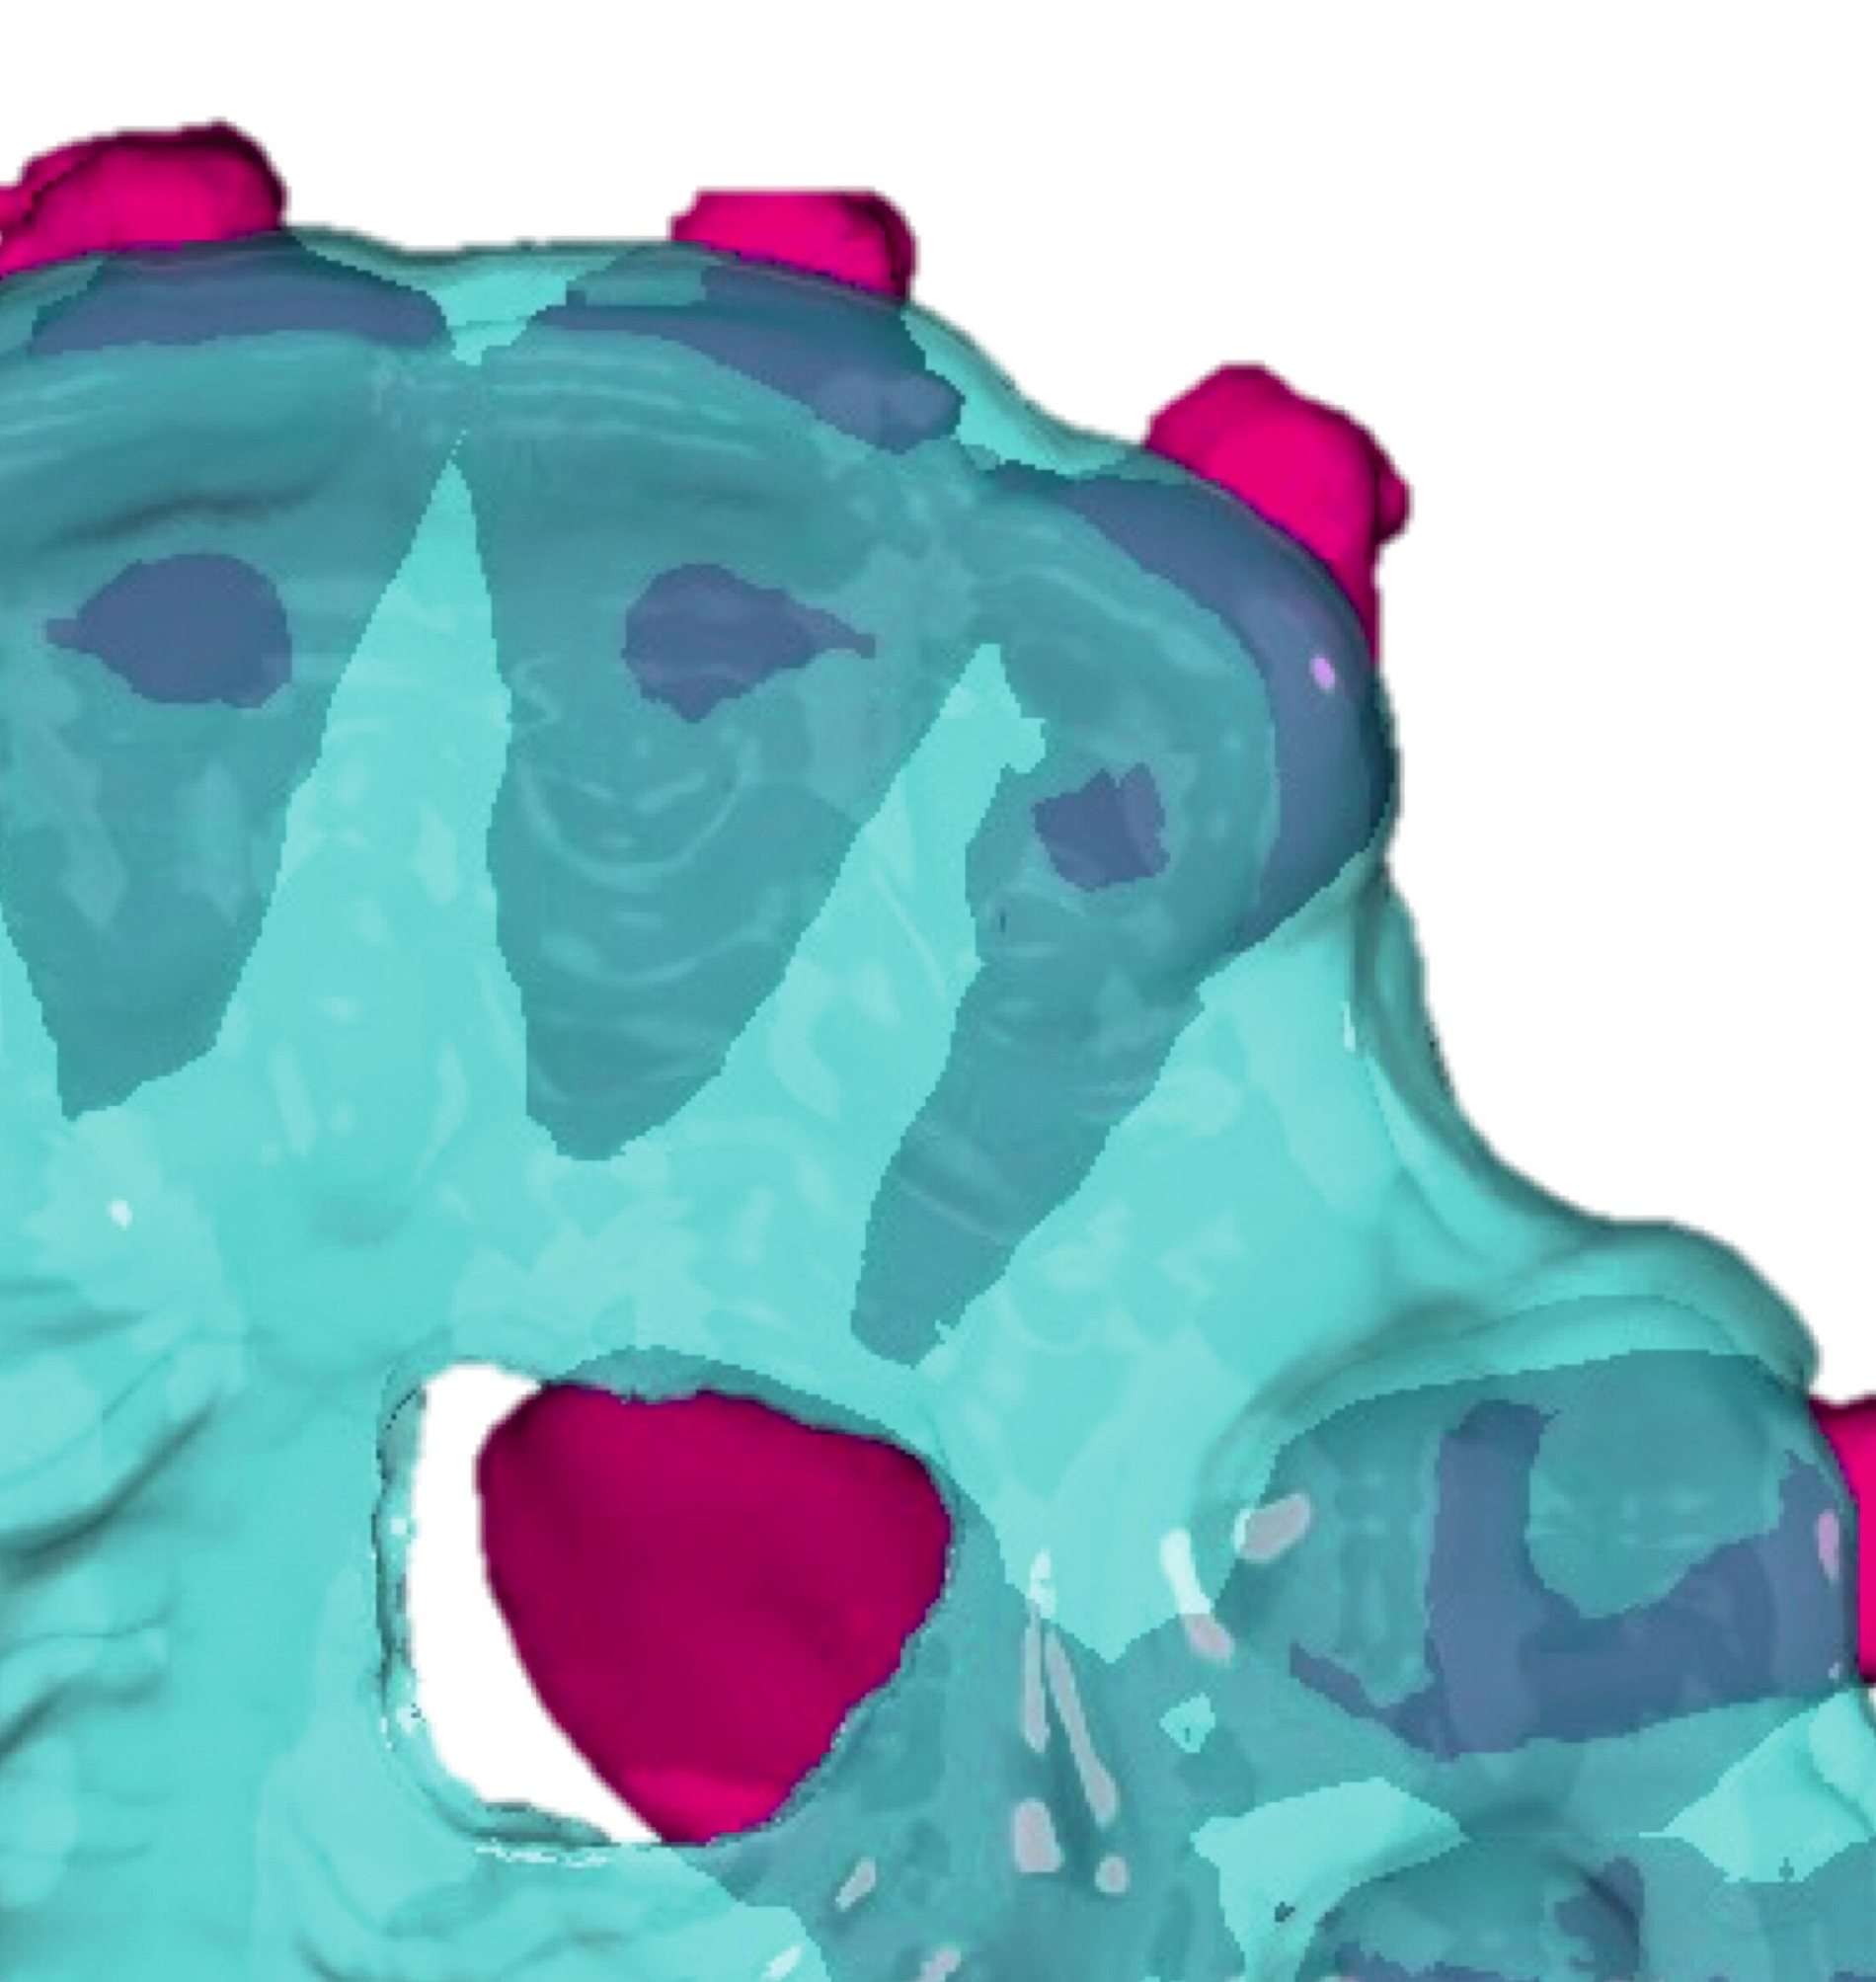

Weitere Beispiele beinhalten hochkomplexe Behandlungsfälle multipler Zahnanlagen. Während die Extraktionsentscheidung und Absprache mit dem/der chirurgisch tätigen Kollegen/in allein auf Basis der Bildgebung oft limitiert ist, erleichtern 3-D-gedruckte Modelle des segmentierten DVTs sowohl die Entscheidung als auch die Absprache und ermöglichen darüber hinaus eine genauere Planung des chirurgischen Vorgehens (Abbildung 6c). Gleiches betrifft parodontalchirurgische Eingriffe, in denen sogenannte „Cutting guides“ eine zuvor digital geplante Gingivektomie ermöglichen (Abbildung 6d). Im Bereich der Freilegung verlagerter Zähne können Schablonen dem/die chirurgisch tätigen Kollegen/in sowohl die Freilegung des Zahnes (Abbildung 6e) als auch die Anbringung eines Attachments (Abbildung 6f) erleichtern und dabei die kieferorthopädisch gewünschte Attachmentposition passgenau übertragen.